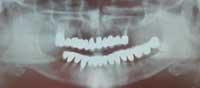

Radiograph of 71-year-old woman before and after implant restoration

The case above is an excellent example in which someone who experiences continued periodontal breakdown around teeth despite treatment will fare better with implants and resist problems with future decay. Dr. Andrew Alpert of Aventura, Fla., placed the implants.